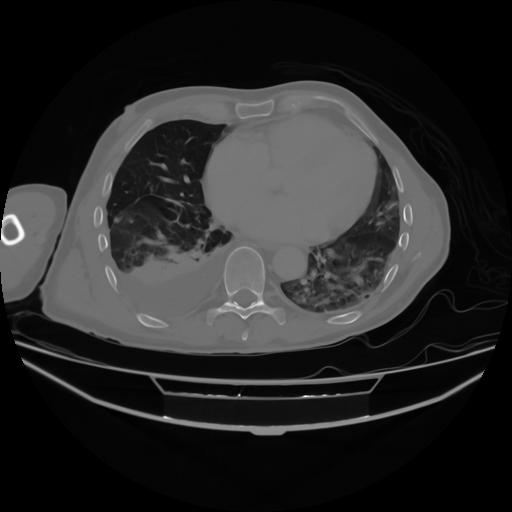

4 CUERPO,CE,Axial,3.0,CUERPO,,